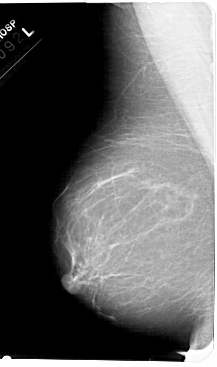

A_1680_1.LEFT_MLO

LEFT_MLO LINES 5491 PIXELS_PER_LINE 3241 BITS_PER_PIXEL 12 RESOLUTION 43.5 NON_OVERLAY